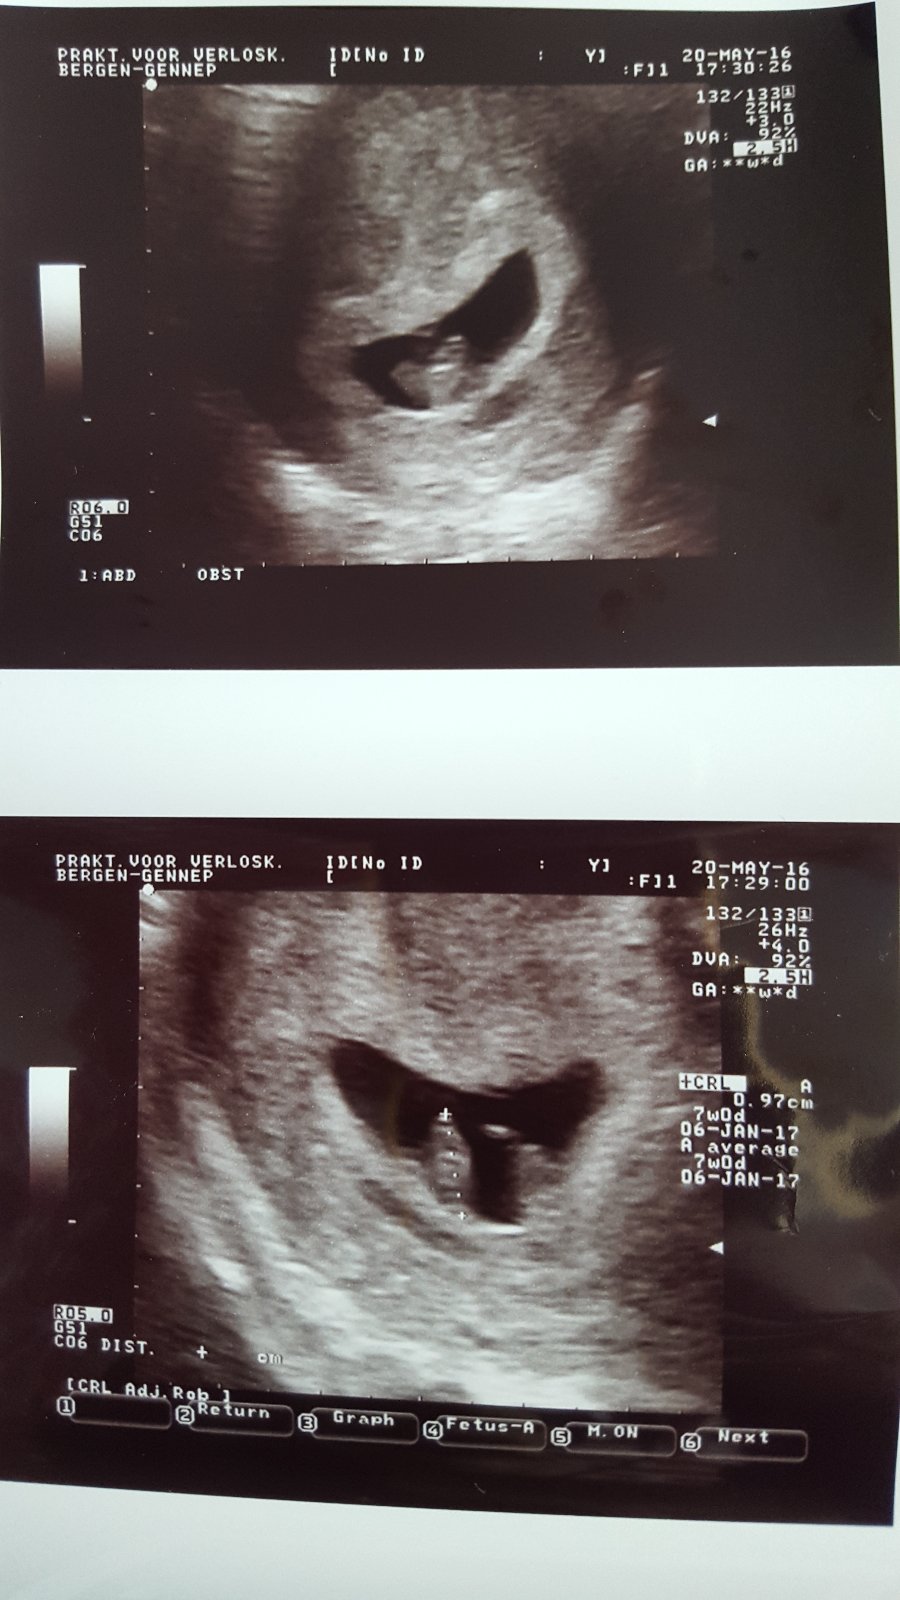

Baby moje,krasne nam bije srdiecko 🙂az som sa rozplakala na ultrazvuku 🙂

Na fotecke mam,ze 6+1 a za tym +-4d.ze som v 7 tt.rano som mala tlak 87/50 a u gyn 125/85🙂to boli stresy.Ale super pocit.Mam stale nizky tlak,mam pit vela vody